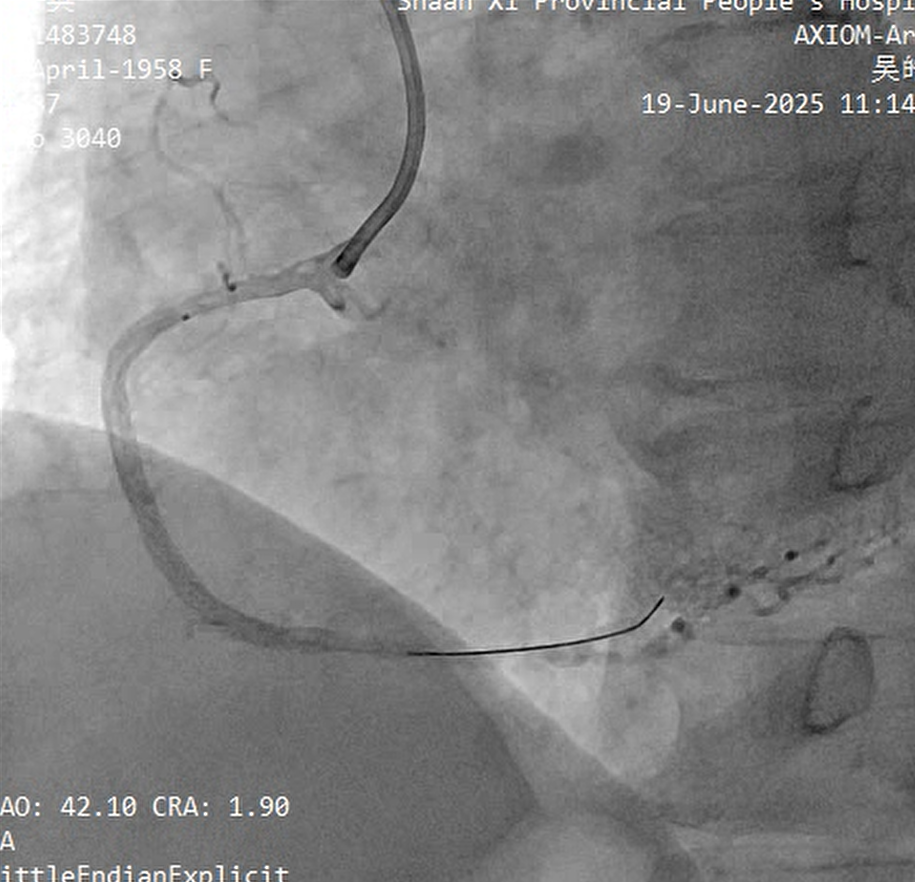

The left coronary lesion was addressed in 7 days, with ECMO support.

LAD:

Neither 0.8 ¡¿ 10 mm nor 1.25 ¡¿ 15 mm balloon could cross the mid LAD lesion; tactile feedback confirmed calcification;

Rotational atherectomy was initiated. However, the microcatheter could only be advanced to the mid segment of the LAD. The rotawire was then exchanged through the microcatheter;

1.25mm Bur£¬a distinct "breakthrough" sensation was felt as the rotablation burr crossed the mid LAD lesion;

During rotational atherectomy, transient coronary no-reflow occurred, accompanied by hypotension and bradycardia.;

The 2.0 ¡¿ 15 mm balloon successfully and smoothly crossed;

LAD 6-8, a 2.0 ¡¿ 24 mm DCB was deployed, followed by the implantation of a 2.75 ¡¿ 20 mm stent and a 3.5 ¡¿ 16 mm stent;

The treatment for the LCX was scheduled for a later stage.